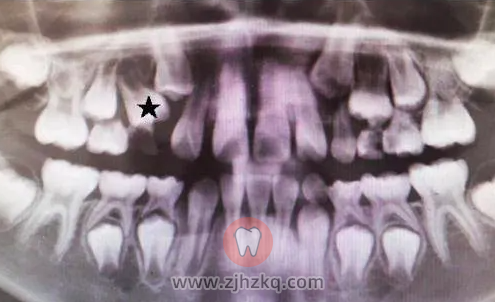

王医生回忆,之前门诊来过一位7岁的小朋友,右上排一个乳牙牙冠已经完全蛀掉。询问家长得知,来就诊的之前几个月,小朋友就已经因为这颗牙齿感染发烧过两次。烧退后也一直未处理该牙,后来因为发现这颗牙齿旁边疑似有新牙长出,才来医院就诊。医生检查发现,孩子的这部分牙龈已经有脓液溢出了,而影像学检查提示上方正在萌出的恒牙牙根才刚刚开始发育。这样的双排牙很可能一个也保不住。